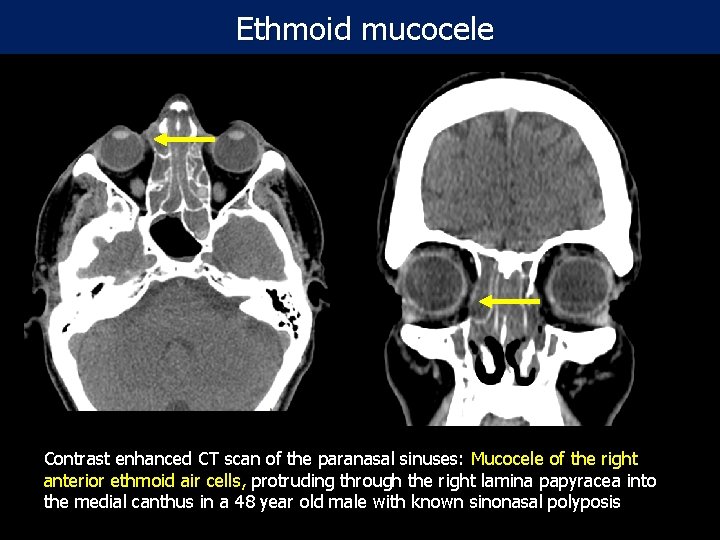

Ethmoid mucocele Contrast enhanced CT scan of the paranasal sinuses: Mucocele of the right anterior ethmoid air cells, protruding through the right lamina papyracea into the medial canthus in a 48 year old male with known sinonasal polyposis